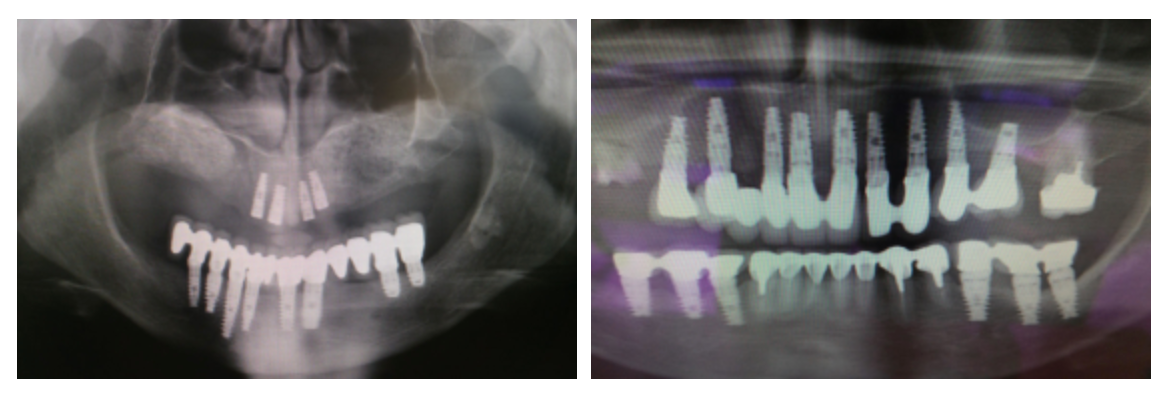

C’est pour cette raison que le praticien adapte la longueur, le diamètre et la forme de l’implant en fonction de chaque cas clinique, en s’appuyant sur des examens radiologiques de haute précision comme l’imagerie 3D ou le scanner.

Le processus commence par la préparation de l’os à l’aide de forets de diamètre adapté. L’implant est inséré avec une légère pression afin d’assurer une bonne stabilité. S’ensuit la phase d’ostéo-intégration, pendant laquelle l’implant, contrairement à une dent naturelle, devient totalement fixe, s’ankylosant dans l’os. Cette étape, cruciale pour le succès de l’intervention, nécessite un délai de plusieurs semaines à plusieurs mois avant la mise en charge définitive.

Enfin, une couronne est placée sur l’implant, qui agit alors comme une racine artificielle, restituant pleinement la fonction et l’esthétique du sourire.